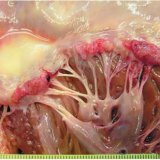

При ревматизме, створки клапанов сердечной мышцы перестают замыкаться в полном объеме, они опухают. На линиях, где смыкаются клапаны сердца, начинают проявляться различного рода эрозии, что в дальнейшем приводит к образованию наростов. Пораженный митральный клапан сердца начинает сужаться, тем самым, провоцируя выброс крови не из желудочка сердца. Кровь начинает возвращаться обратно в предсердие.

Также при ревматизме появляются некие наросты по краям клапанов, которые образовываются из фибрина (один из важнейших составляющих тромбов) и пластинок (кровяные клетки, отвечающие за свертывание крови).

На сегодняшний день, участились случаи обострения заболевания клапанов сердца, вызванные частыми приступами атак ревматизма. В этом случае, изменение митрального клапана переходит в заболевание, которое называется «митральный стеноз». При таком заболевании отверстие клапанов существенно сужается, происходит зарастание сухожильных хорд (с их помощью створки клапанов прикрепляются к мышечным камерам самого сердца), вследствие чего значительно сокращается подвижность клапанов.